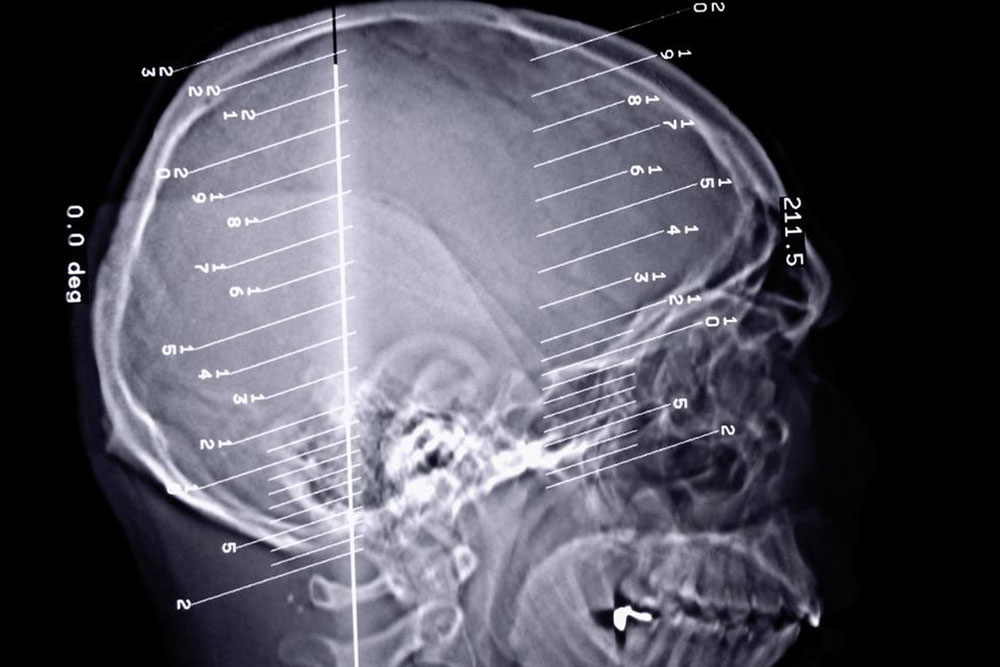

Epilepsy is a dreaded disorder, especially since it is connected to the dysfunctioning of the brain. The brain plays a pivotal role in the functioning of the human body and any kind of issue can lead to severe complications. The disorder is related to the dysfunctioning of the central nervous system in the brain.